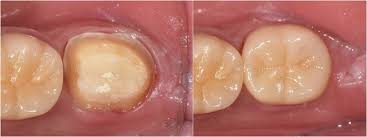

신경치료 후 치아는 내부 구조가 약해져 쉽게 깨질 수 있습니다. 크라운은 이를 보호하고, 씹는 기능과 심미성을 복원해주는 중요한 치료 단계로, 선택이 아닌 필수입니다.

크라운은 손상된 치아 위를 씌우는 인공 보철물로, 치아를 외부 충격에서 보호하고 정상 기능과 자연 외형을 회복시켜 줍니다. 어금니는 내구성, 앞니는 심미성을 고려해 재료를 선택하는 것이 핵심입니다.